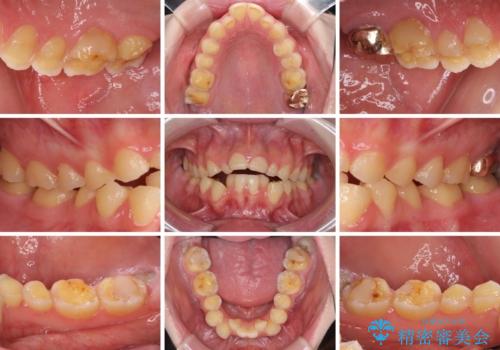

- 一時期の拒食症に伴い歯が酸で溶けてボロボロになってしまったとのことで来院された患者様です。

酸によりエナメル質の大半が溶けており、下顎前歯以外は酷いむし歯のような状態でした。

当初はほとんどの歯をむし歯治療のようにオールセラミッククラウンにて補綴治療を行う予定でしたが、仮歯に置き換えた時点で、口元の突出感や下顎前歯の叢生が気になるとのことで、上下左右の第一小臼歯4本を抜歯したワイヤー装置での抜歯矯正を行うこととしました。

矯正治療終了後に、残った歯をオールセラミッククラウンにて補綴治療を行うこととしました。

途中来院が困難な時期があったり、歯周外科処置を行って治癒を待ったりと、治療期間は長くなりましたが、初診時とは比べものにならないくらいきれいに仕上げることができました。